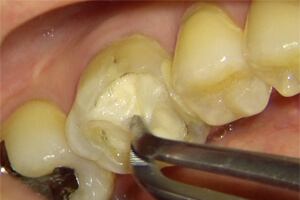

5

感染(虫歯など)のみに色がつく染色液です。神経は取れていますが、感染が残ってしまい痛みが残っていました。

6

虫歯を除去し再度バイ菌が入らないよう壁を作ると痛みは無くなりました。(隔壁と言います)